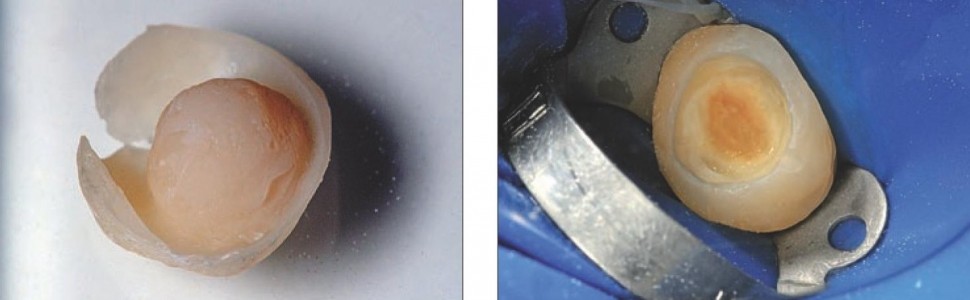

Usunięto nieszczelne wypełnienie klasy I, ubytek oczyszczono z tkanki próchnicowej (ryc. 1). Na podstawie wax-upu (ryc. 2) wykonano transparentny indeks silikonowy (Elite Glass, Zhermack), który przymierzono na opracowany ząb 27 (ryc. 3). Indeks zdjęto z zęba, ubytek i ściany zewnętrzne posmarowano cienką warstwą żelu glicerynowego. Do indeksu nałożono materiał kompozytowy Estelite Posterior PA3 (Tokuyama Dental), dokładnie skondensowany, w jednej warstwie. Indeks z nałożonym niespolimeryzowanym materiałem wprowadzono ponownie na ząb, dociskając tak, by uzyskać sprawdzone wcześniej stabilne położenie, a tym samym doprowadzić do wypłynięcia nadmiarów kompozytu. Zastosowany materiał kompozytowy umożliwia wygodną i spokojną pracę, bez ryzyka wcześniejszej polimeryzacji, a jego właściwości fizyczne dają pewność co do odpowiedniej wytrzymałości mechanicznej wykonanego uzupełnienia. Po usunięciu nadmiarów materiał spolimeryzowano światłem lampy polimeryzacyjnej, poprzez transparentny indeks silikonowy, 60 sekund z każdej strony. Zdjęto indeks, a każdą powierzchnię znajdującej się na zębie odbudowy dodatkowo doświetlono. Następnie odbudowa została ostrożnie podważona zgłębnikiem w celu jej usunięcia z ubytku. Uwolnioną pracę (ryc. 4) dodatkowo doświetlono od strony wewnętrznej. Wykonaną odbudowę odtłuszczono, przemywając ją alkoholem izopropylowym. Gdy stosuje się metodę półpośrednią, nie stanowią problemu wycienienia odbudowy, w tym wypadku widoczne na powierzchni zgryzowej i przedsionkowo. Były one odwzorowaniem cienkiej warstwy wosku nałożonego na modelu, co wynikało z sytuacji klinicznej. Gdyby jednak – w innym przypadku – istniała potrzeba nadbudowy takich miejsc (np. gdyby niedomiar powstał na skutek uszkodzenia pracy przy jej uwalnianiu z zęba), na kolejnym etapie mogłyby one zostać uzupełnione tym samym materiałem kompozytowym, z którego praca została wykonana.